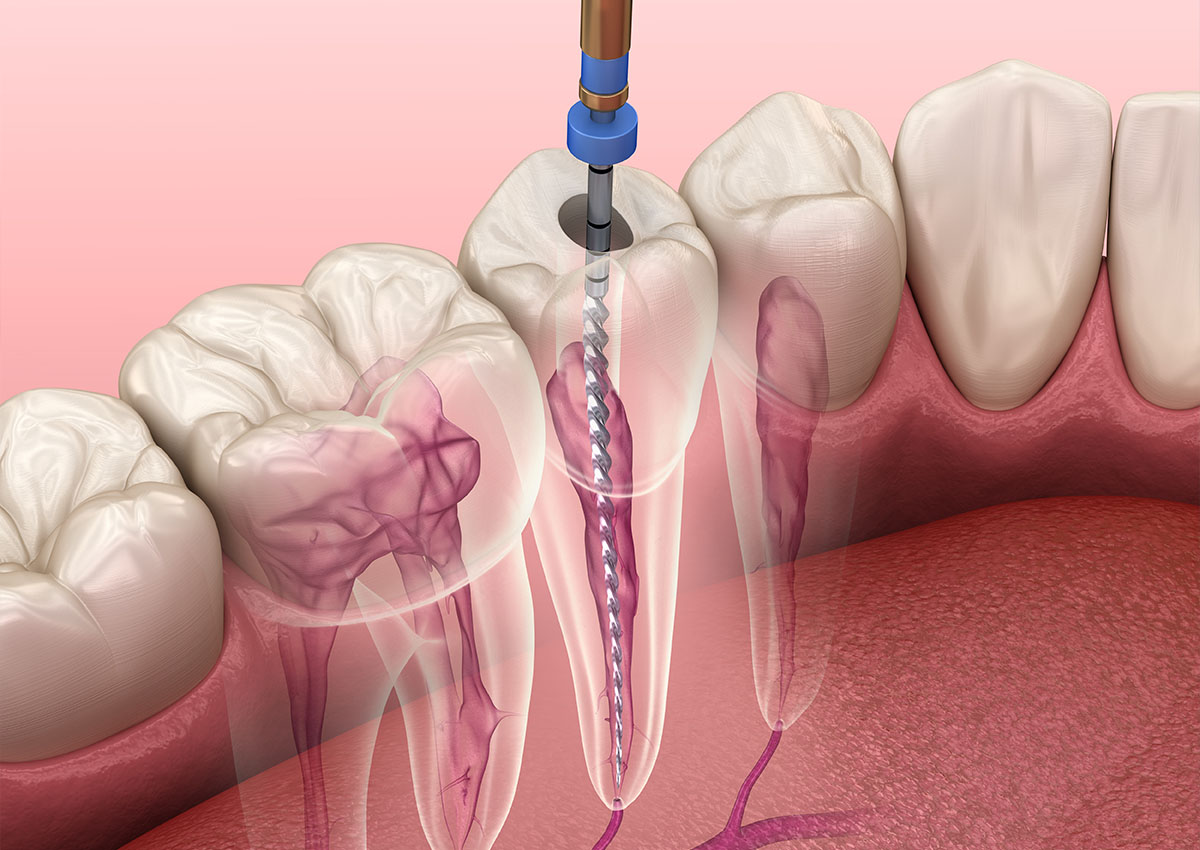

Saving or repairing a natural tooth is always our preferred option. The most common method to achieve this is root canal treatment, known as endodontics. The procedure involves removing damaged or dead pulp in the tooth root and filling the space with a sealer paste and a rubber compound. The tooth can then be rebuilt, usually with a crown, to ensure it remains part of your dentition for a long time.